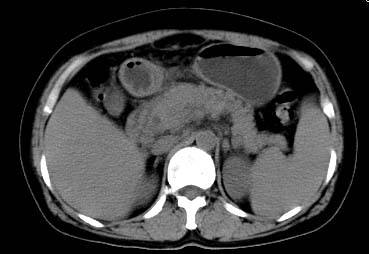

以下是引用西北一只狼在2008-6-30 20:58:00的发言:[br]肝左叶胆管细胞ca并肝门淋巴结转移、胰腺、胃小弯浸润

以下是引用ydx_74在2008-6-30 21:54:00的发言:[br]左叶胆管细胞ca并肝门淋巴结转移、胰腺、胃小弯浸润